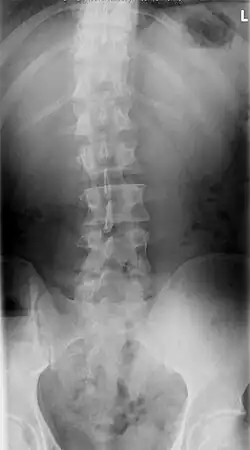

Scoliose (Grieks: σκολιός, skolios = krom) is een zijdelingse verkromming van de wervelkolom, die dan één of twee bochten vertoont. De vroegst bekende beschrijving van scoliose dateert uit de 3e-4e eeuw v.Chr.

Men onderscheidt een S-vormige scoliose met twee bochten en een C-vormige scoliose met één bocht. Een S-scoliose benoemt men naar de convexe (bolle) kant van de grootste bocht; bijvoorbeeld een S-vormige thoracale scoliose, rechts convex van 35 graden. De wervelkolom is meestal tevens om zijn as gedraaid, men spreekt dan van een torsiescoliose, waardoor een bochel (gibbus) ontstaat. Hoewel het een ingewikkelde driedimensionale vervorming betreft, kan men op een gewone voor-achterwaartse röntgenfoto de zijdelingse verkromming goed zien als een C-vormige of een S-vormige slinger in de ruggengraat die eigenlijk een rechte lijn behoort te zijn. Een structurele scoliose zal meestal gepaard gaan met een draaiing, een torsie; ook een bijkomende voorovergebogen houding (kyfose), een holle rug (lordose) of beide komen vaak samen met de scoliose voor. Belangrijk is of de scoliose in evenwicht is, dat wil zeggen of het zwaartepunt van het lichaam tussen de voeten valt. Als de wervelkolom van de patiënt een S-vormige bocht heeft, kan zich op borsthoogte een convexe bocht naar rechts bevinden en op lendenniveau een convexe bocht naar links. Meestal heffen de bochten elkaar op. Indien dit niet het geval is, bestaat er een grote kans op verergering.

Voor operatie -